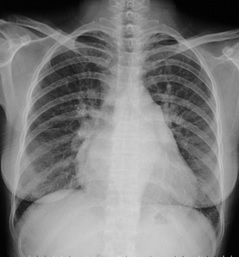

试题:根据下图请做出正确诊断

影像诊断

A.正常心脏

B.心肌病(普大心)

C.风湿性心脏病(梨型心)

D.主动脉型心(靴型心)